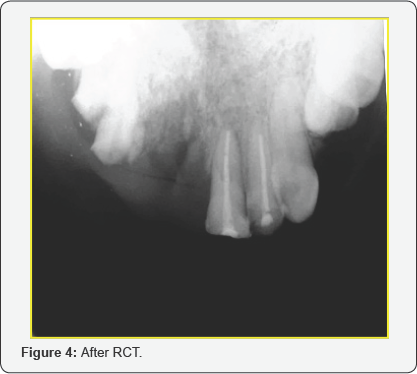

A 25 yrs old serving soldier reported to our center with severe mid facial injury due to Gun shot. On examination he was conscious, alert and oriented to time, place and person. His upper lip was torn in to two (degloving injury of the upper lip),nasal aperture shattered, dorsum was injured and his bridge of the nose was flattened (Figure 1). On intra oral examination there was avulsion of Upper anteriors on the right side and the left anteriors of the maxillary arch were fractured. Initially after stabilization the patient was subjected to CT scan and radiographs to rule out any injury to skull, brain and other bony injuries. After confirming there was no bony injury, a multidisciplinary approach was planned for comprehensive management. Patient was taken up under general anesthesia with oral intubation. Initially debridement was done and soft tissue closure was carried out in layers using 3-0 vicryl (Figure 2). The lip and nasal deformities were successfully corrected using a nasolabial flap. An inferiorly based nasolabial flap was designed. In this case the distal end of the flap is thinned by defatting and the distal part is folded and used as an inner lining. The inner layer sutured from proximal to distal by absorbable suture (4-O Vicryl) and the outer layer is sutured by (5-O Prolene). Care was taken to preserve the intervening skin bridge representing the nasofacial aesthetic line. To maintain the nasal patency and to retain the contour of the dorsum of the nose and nostrils, soft tissue closure was carried out with nasal stents placed inside the nostrils. Pressure dressing was placed and checked postoperatively. Sutures are removed after 5-7 days postoperatively. The right maxillary anteriors, tooth no 11, 12 and 13 which were fractured, avulsed and beyond restorable were extracted (Figure 3). The fractured teeth no 21 and 22 were root canal treated (Figure 4), core build up was done and porcelain fused to metal crown was placed. The missing teeth on the right maxillary arch which were extracted were prosthetically restored by using removable acrylic partial denture (Figure 5). There were multiple surgeries carried out by the Plastic surgery department. The patient underwent successive surgeries to get the final and better soft tissue shape and characteristic for both nostrils. Follow up was done for a period of one year and there were no post-operative or rehabilitative complications (Figure 6).